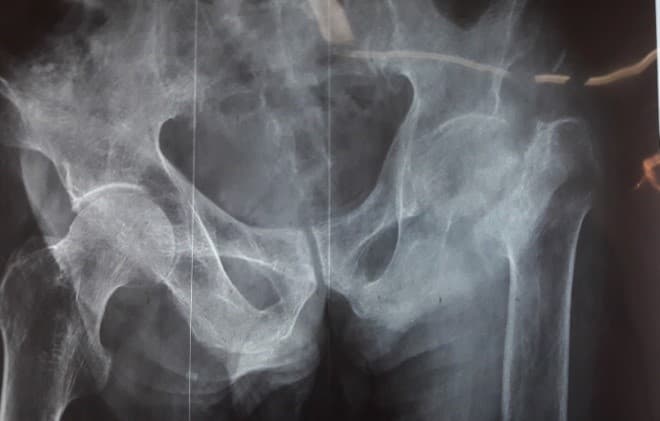

Мэс заслын өмнөх болон дараах рентген зураг